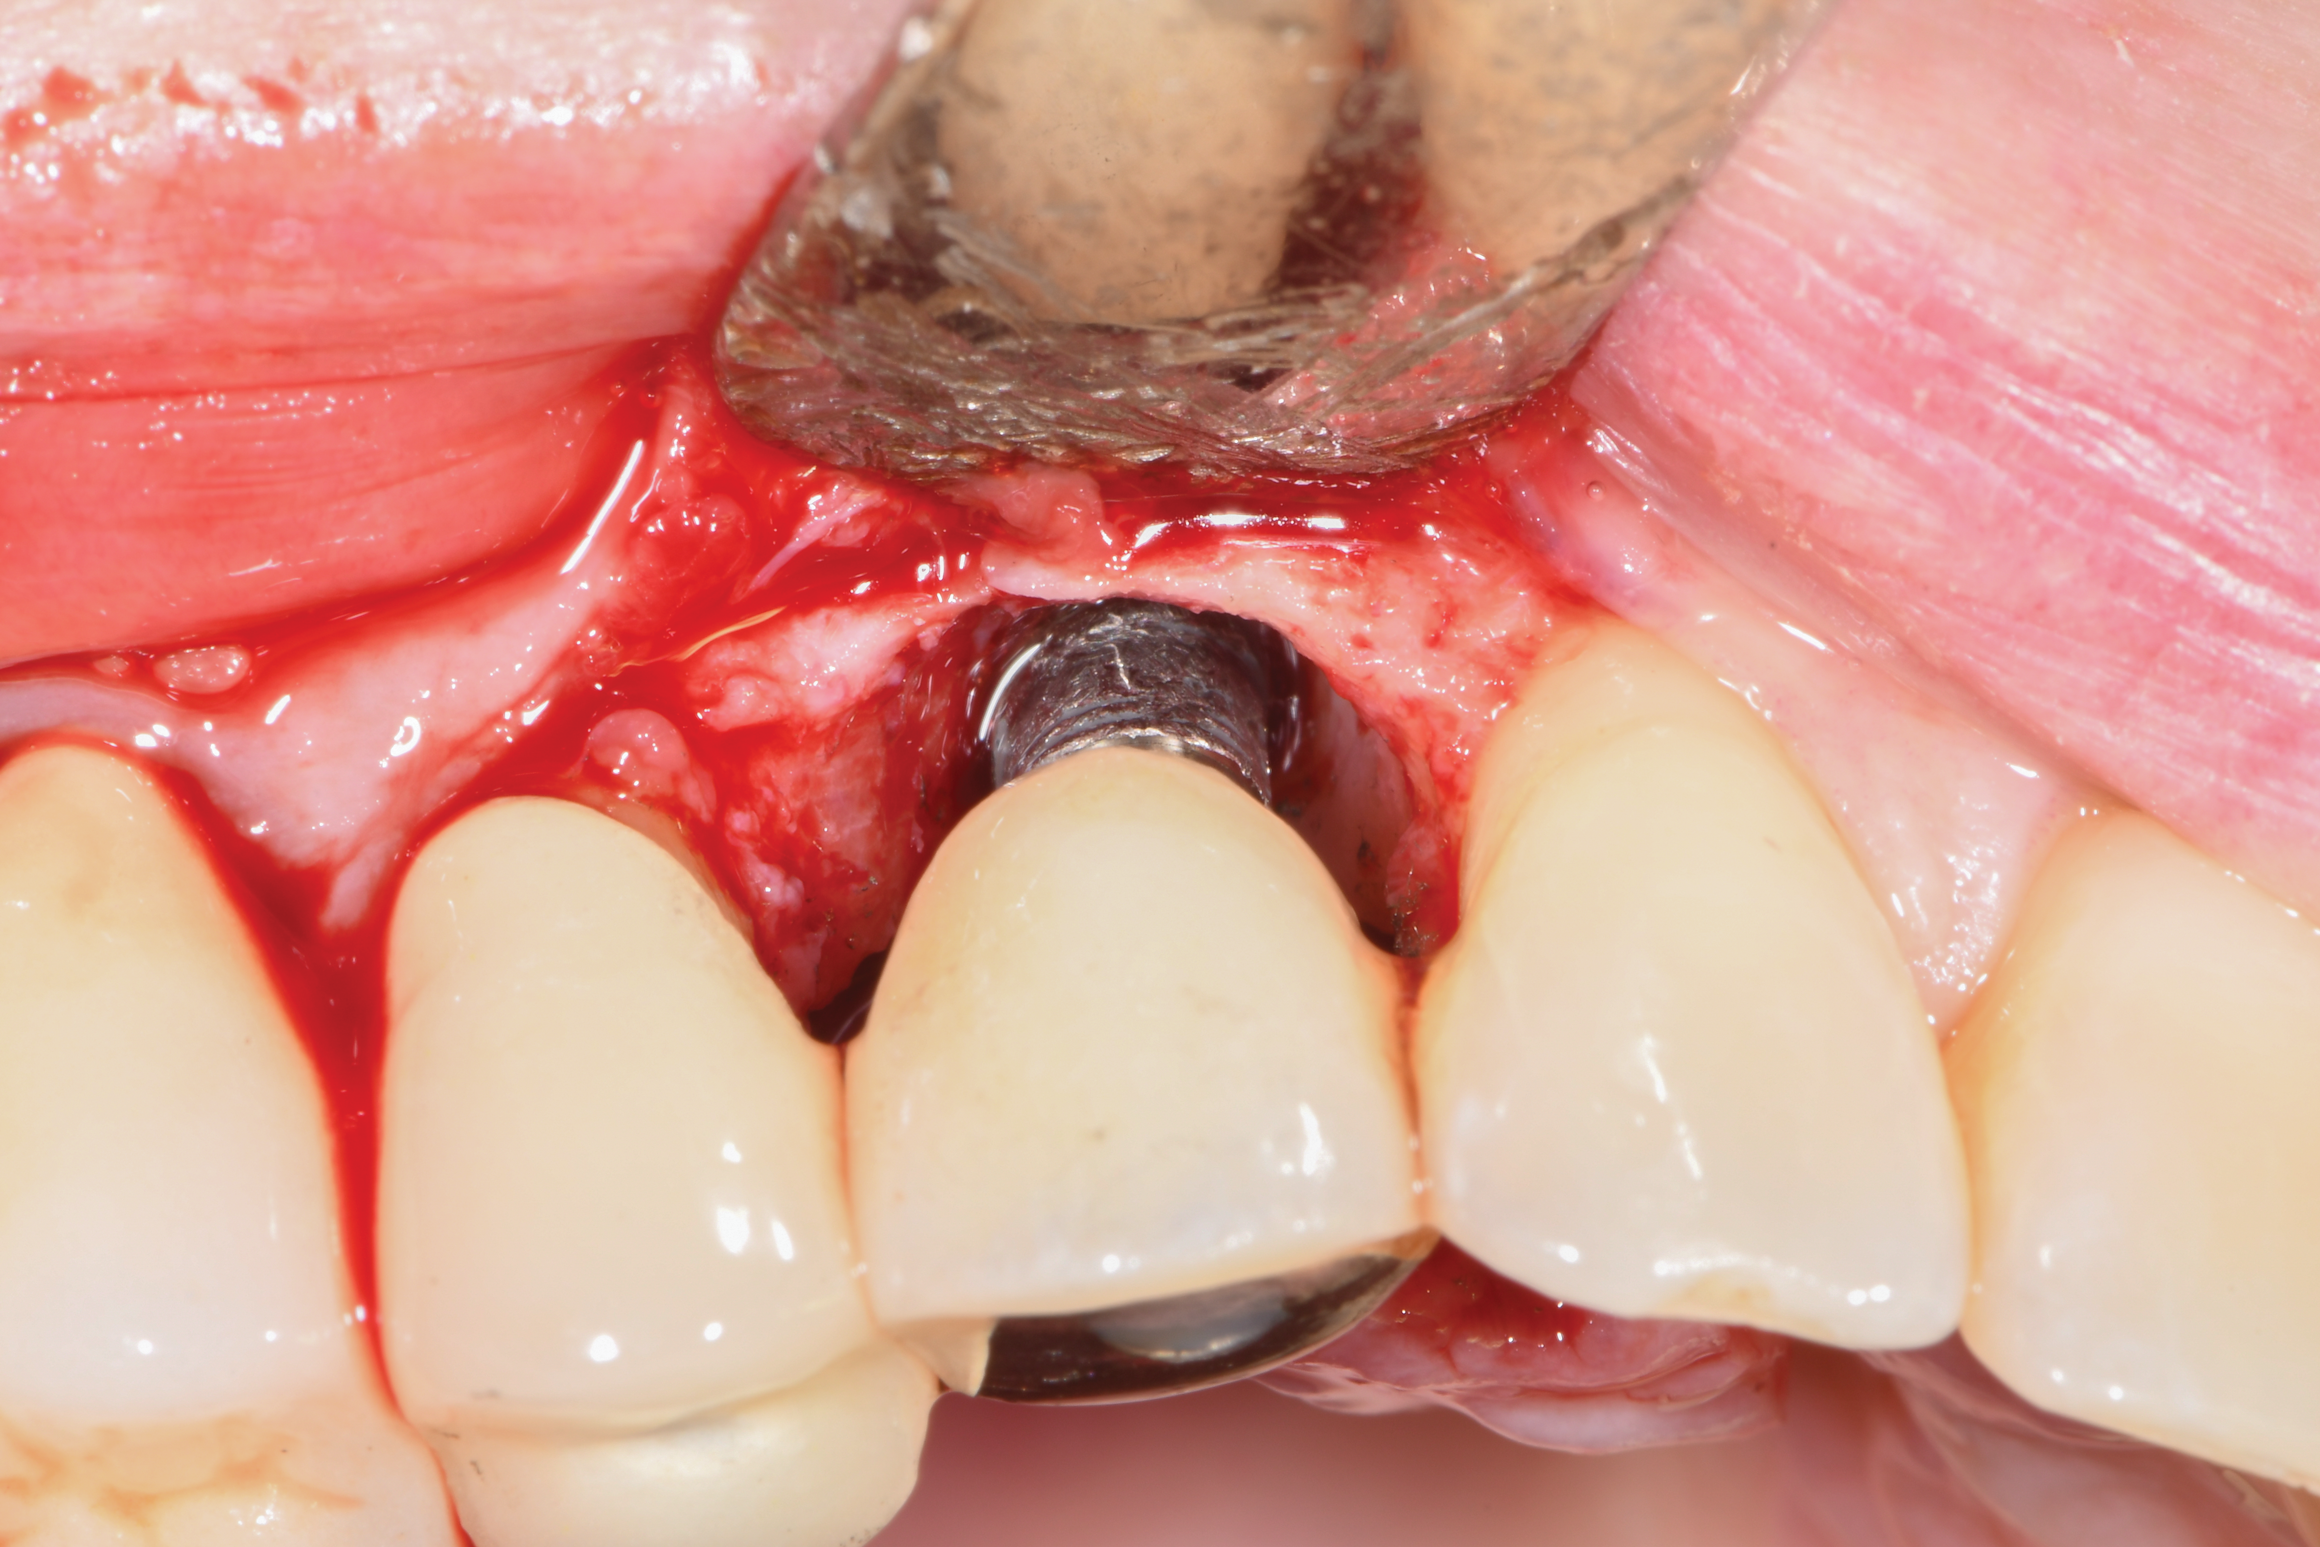

A surgical approach was planned that included implantoplasty and guided bone regeneration. After local anesthesia was administered, full-thickness flaps were elevated using an envelope flap on the buccal aspect and a triangular design on the palate to expose the defects. Removal of granulomatous tissue from the area enabled visualization of a narrow circumferential lesion on the facial (Figure 3) and a one- to two-wall combination defect on the palatal (Figure 4). The surface was initially treated with a 50% solution of citric acid for 30 seconds followed by thorough rinsing with sterile saline. This was followed by implantoplasty using a 30-fluted finishing bur of surgical length. Because the implant was very narrow, achieving a matte-like surface was not possible; thus, the goal was to reduce the threads and lightly remove the implant's outer surface to expose fresh titanium (Figure 5 and Figure 6). The modified surface was treated again with citric acid and rinsed with sterile saline.

Fig 3. A narrow three-wall infrabony defect was visualized on the facial of the implant.

Figure 3

Fig 4. Two-wall bony lesions were visualized at the mesio- and distopalatal aspects. The black marks seen on the implant surface were from prior laser treatment.

Figure 4